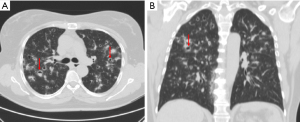

Mycobacterium TB infection

Cavitation is a hallmark of post-primary TB, occurring in approximately 50% of patients (7). The likelihood of cavitation correlates with higher sputum mycobacterial loads (8). Moreover, cavitation is an uncommon feature of primary TB, which is characterized by inflammation and granuloma formation that does not usually lead to the tissue destruction that causes cavitation (8,17). Cavitation primarily occurs in post-primary TB, when the bacteria reactivate from dormant state and the immune system’s response leads to more extensive tissue damage and cavitation (8,17). Hence, radiologically, primary TB is more likely to show intra-thoracic lymph node enlargement, pleural effusion and lower lobe lung lesions. Cavitation is less characteristic of these initial presentations, seen only in 10–30% of cases (17). Typical imaging findings of post-primary TB include a predilection for the upper lobes, particularly the apical and posterior segments (7). Patchy and poorly defined consolidations are often the earliest findings (7,8). Cavities often form within areas of consolidation, exhibiting variable wall thickness, ranging from thin and smooth to thick and nodular walls (Figures 7-9) (8). Air-fluid levels are seen in 10–20% of tuberculous cavities (18). Endobronchial dissemination can lead to tree-in-bud opacities, and pleural effusion is common (8).